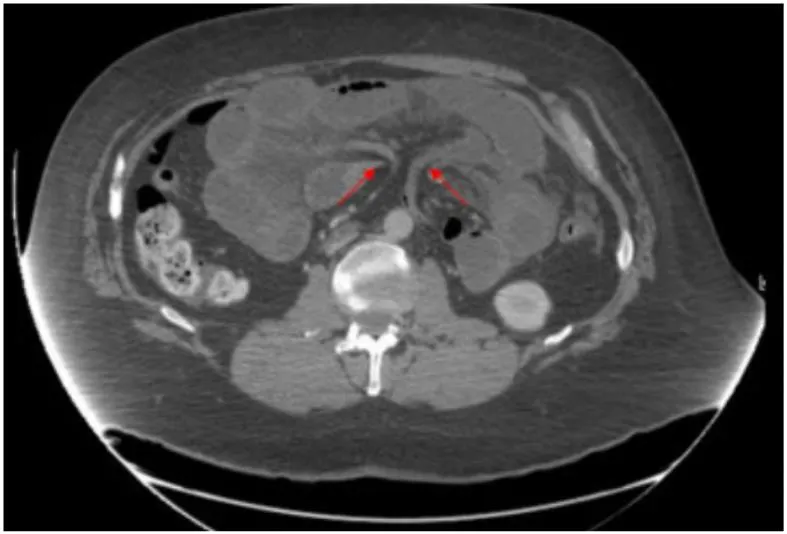

SMV beaking / Criss cross appearance

Mushroom sign : SMA와 distal mesentery vessel branch 사이 좁은 공간으로 mesenteric root가 지나가는데, 버섯처럼 보여서

: Mesenteric swirl, small bowel obstruction 이 internal hernia진단에 있어 가장 정확도가 높다고

알려져 있으나, SMV의 직경이 새부리 모양처럼 줄어드는 SMV beaking sign 역시 흔하게 나타나는 sign이다.

a,b : 소장 loop가 복부 전벽에 인접하여 있다. SMV의 직경이 좁아져 beaked 모양으로 보인다 (화살촉)

herniated mesenteric loop 가 버섯 모양처럼 보인다.